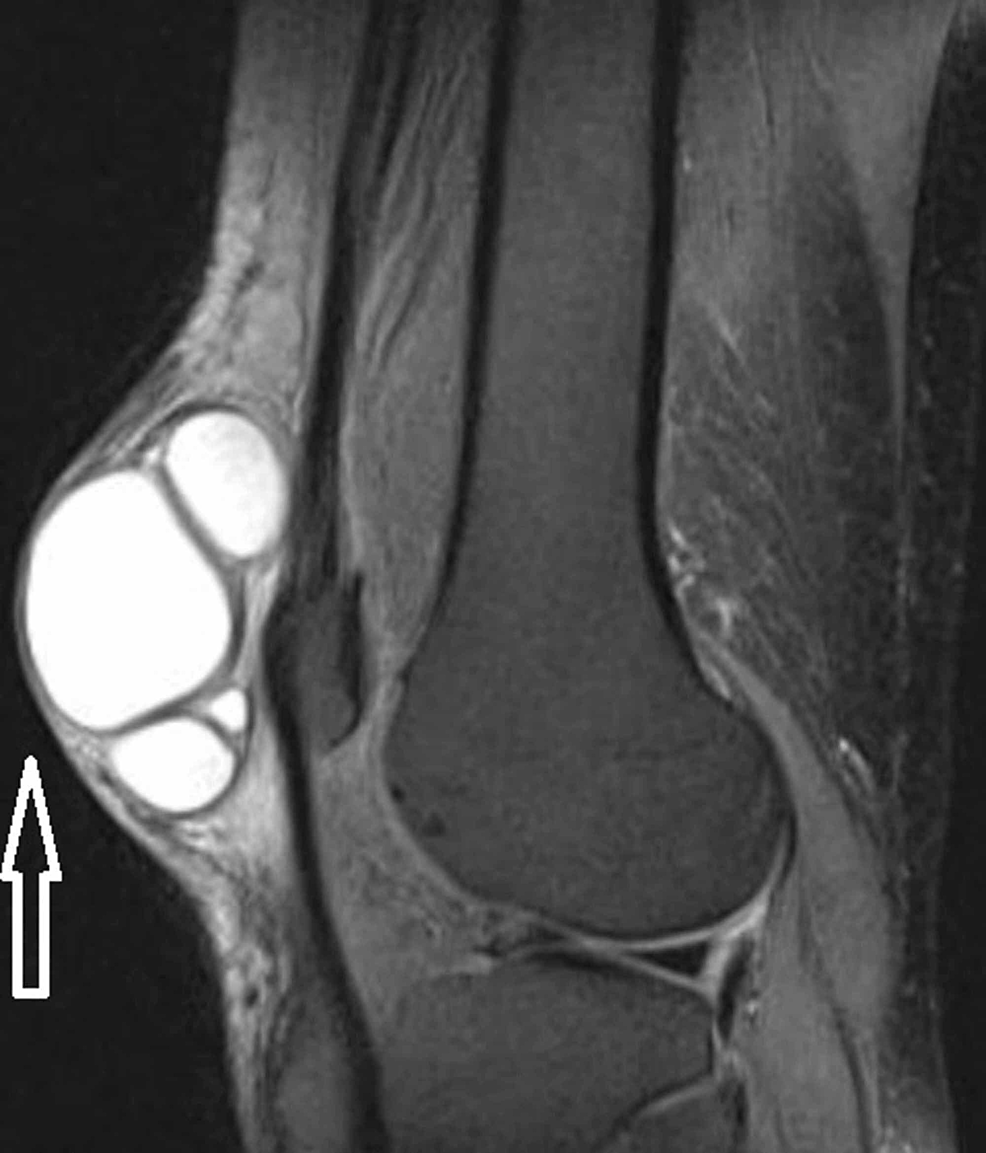

Knee soft tissue swelling sebaceous cyst Radiology Case Sebaceous Cyst Knee last revised by yuichiro hirano on 21 mar 2024. a meniscal cyst is a collection of joint fluid (also called synovial fluid) that forms when there is a tear within the. a sebaceous cyst is a benign growth that forms from your sebaceous gland. They’re usually harmless and don’t need. these are occasionally termed sebaceous cysts,. Sebaceous Cyst Knee.

Get 17 Baker Cyst Mri Knee Sebaceous Cyst Knee Sebaceous cysts are common growths under the skin. Citation, doi, disclosures and article data. It may occur on your knee or other. They’re usually harmless and don’t need. these are occasionally termed sebaceous cysts, although this is a misnomer as the lesion does not originate in the sebaceous glands. last revised by yuichiro hirano on 21 mar 2024.. Sebaceous Cyst Knee.